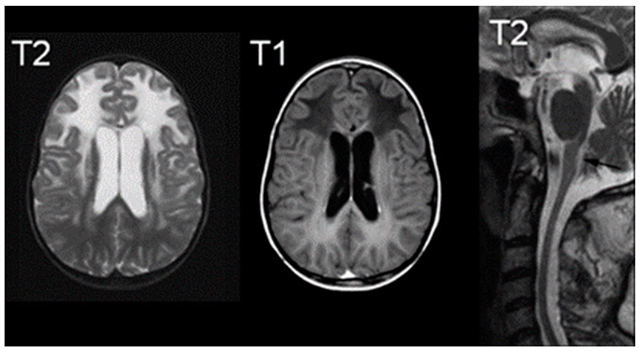

• MRI 诊断标准:满足广泛额叶白质异常、脑室周围边缘信号改变、基底节与丘脑受累、脑干异常、病灶强化 5 项中 4 项即可确诊。

亚历山大病典型的磁共振成像表现;右侧图像显示 T2 信号增高,中间图像显示 T1 信号减低,右侧图像为 T2 中线矢状位切面,可见萎缩征象